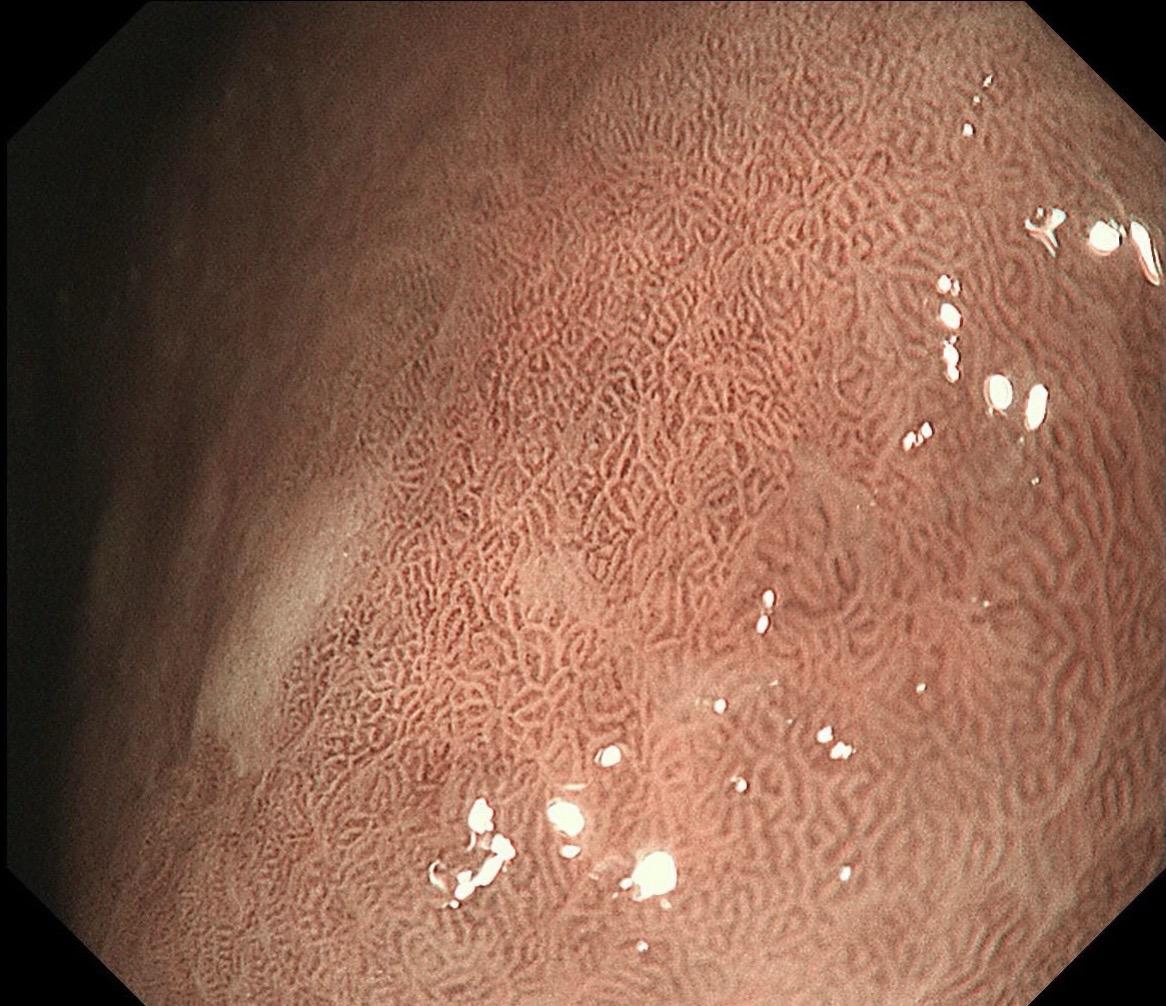

男,40岁,胃双发褪色调病变。慢性胃炎复查,3年前胃镜未见异常,Hp阳性背景,萎缩不明显,胃体下部大弯见一褪色调病变,浅凹陷,5mm左右,换用放大内镜观察,表面结构缺失,血管异型明显,未分化可能性大……胃窦后壁见一白斑,无高度差,NBI浅茶色,放大草草看了下,似有边界,IP增宽,活检待病理……小哥哥胖得几乎没脖子,腹式呼吸太明显~😖